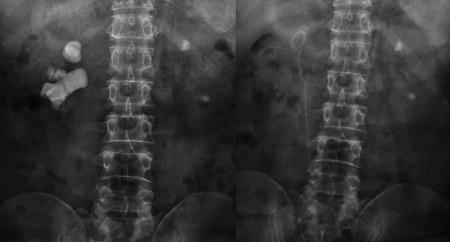

宋先生术前与第二次术后的结石对比“我两个肾脏都长结石,到现在已经长了30年了。自从2000年做了开刀取石后,前前后后做了100多次体外碎石,结石还是疯长不停。”近日,在四川结石病医院泌尿外科病区,来自四川沐川县的宋先生告诉记者,他的肾脏不知怎么回事,每隔个一两年就长出体积骇人的“巨大”结石。

又进行了20多次体外碎石后,肾结石非但没打掉,反而长到了骇人的8公分:X光片里面形似一颗“老姜”,几乎塞满了右肾内的大小通道。

“泌尿道梗阻;右肾多发结石、中度扩张积水;左肾结石伴左肾积水,左肾缩小。”医院的检查结果显示,结石充满了宋先生的右肾,右肾功能受结石和积水的影响,仅剩4成左右,而左肾则出现了可怕的肾萎缩。而这些正是在宋先生接受了惊人的100多次体外冲击波碎石,累计花掉20多万元后,付出的沉重代价。

在经历了两次微创经皮肾镜碎石取石手术后,宋先生右肾内的巨大结石被粉碎并清除,解除了尿路的梗阻,肾脏的积水随之消退。目前,宋先生即将康复出院。